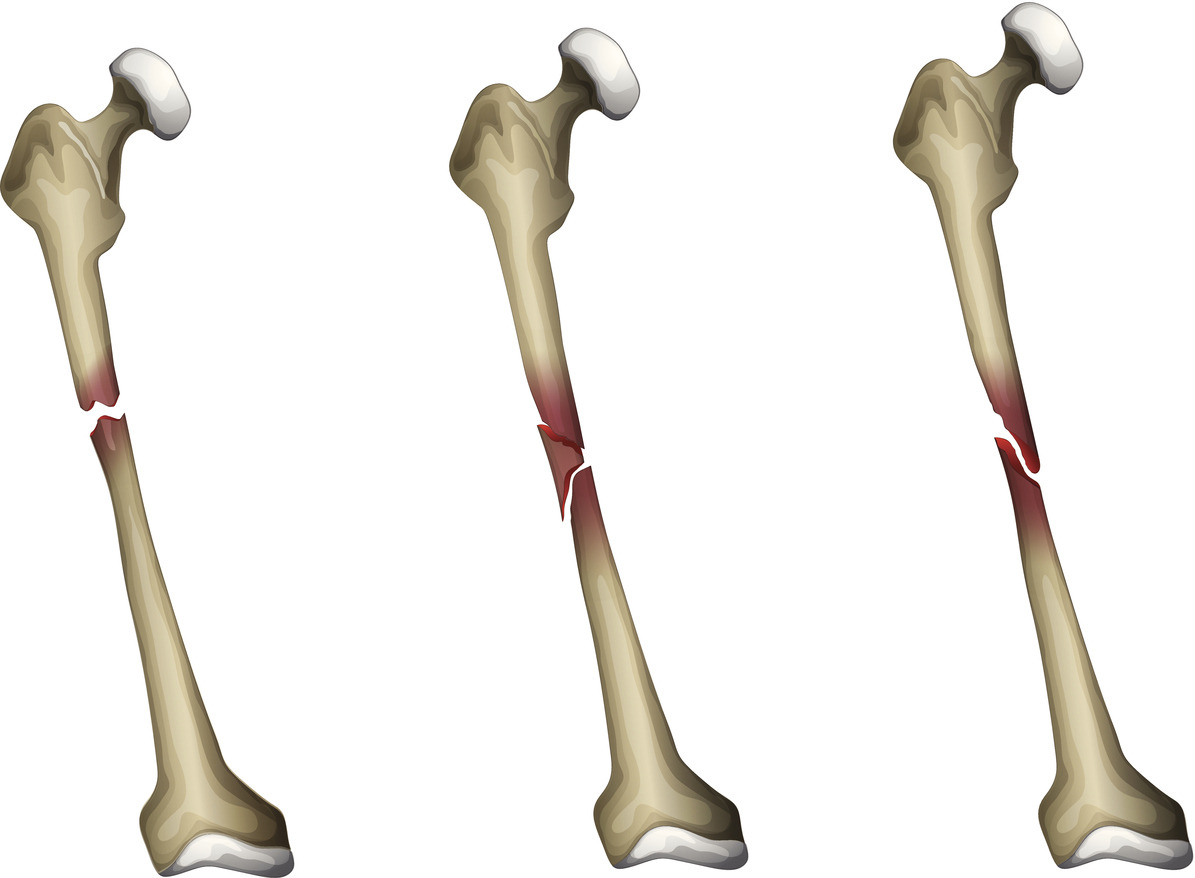

골절의 종류

골절은 크게 개방성 골절과 폐쇄성 골절로 나뉘는데, 개방성 골절은 말 그대로 골절된 뼈가 피부를 뚫고 나와 외부에서 눈으로 직접 관찰되는 골절, 폐쇄성 골절의 경우 뼈의 손상 정도와는 상관없이 골절된 뼈가 피부 밖으로 돌출되지 않아 눈으로 직접 확인이 불가능한 상태의 골절을 의미한다.

기본 형태별

완전 골절 : 뼈의 연속성이 완전히 끊어진 상태

불완전 골절 : 뼈의 연속성은 유지되지만, 부분적으로 혹은 한 쪽면이 손상된 상태

세부 손상 형태별

평면형 골절 : 뼈의 횡단면과 평행하게 발생된 골절

대각선형 골절 : 뼈의 횡단면과 평행하지 않게 대각선으로 발생된 골절

조각 골절 : 뼈의 일부 혹은 전체가 조각난 골절

나선형 골절 : 뼈의 가운데 축을 중심으로 나선형으로 틀어지며 손상된 골절